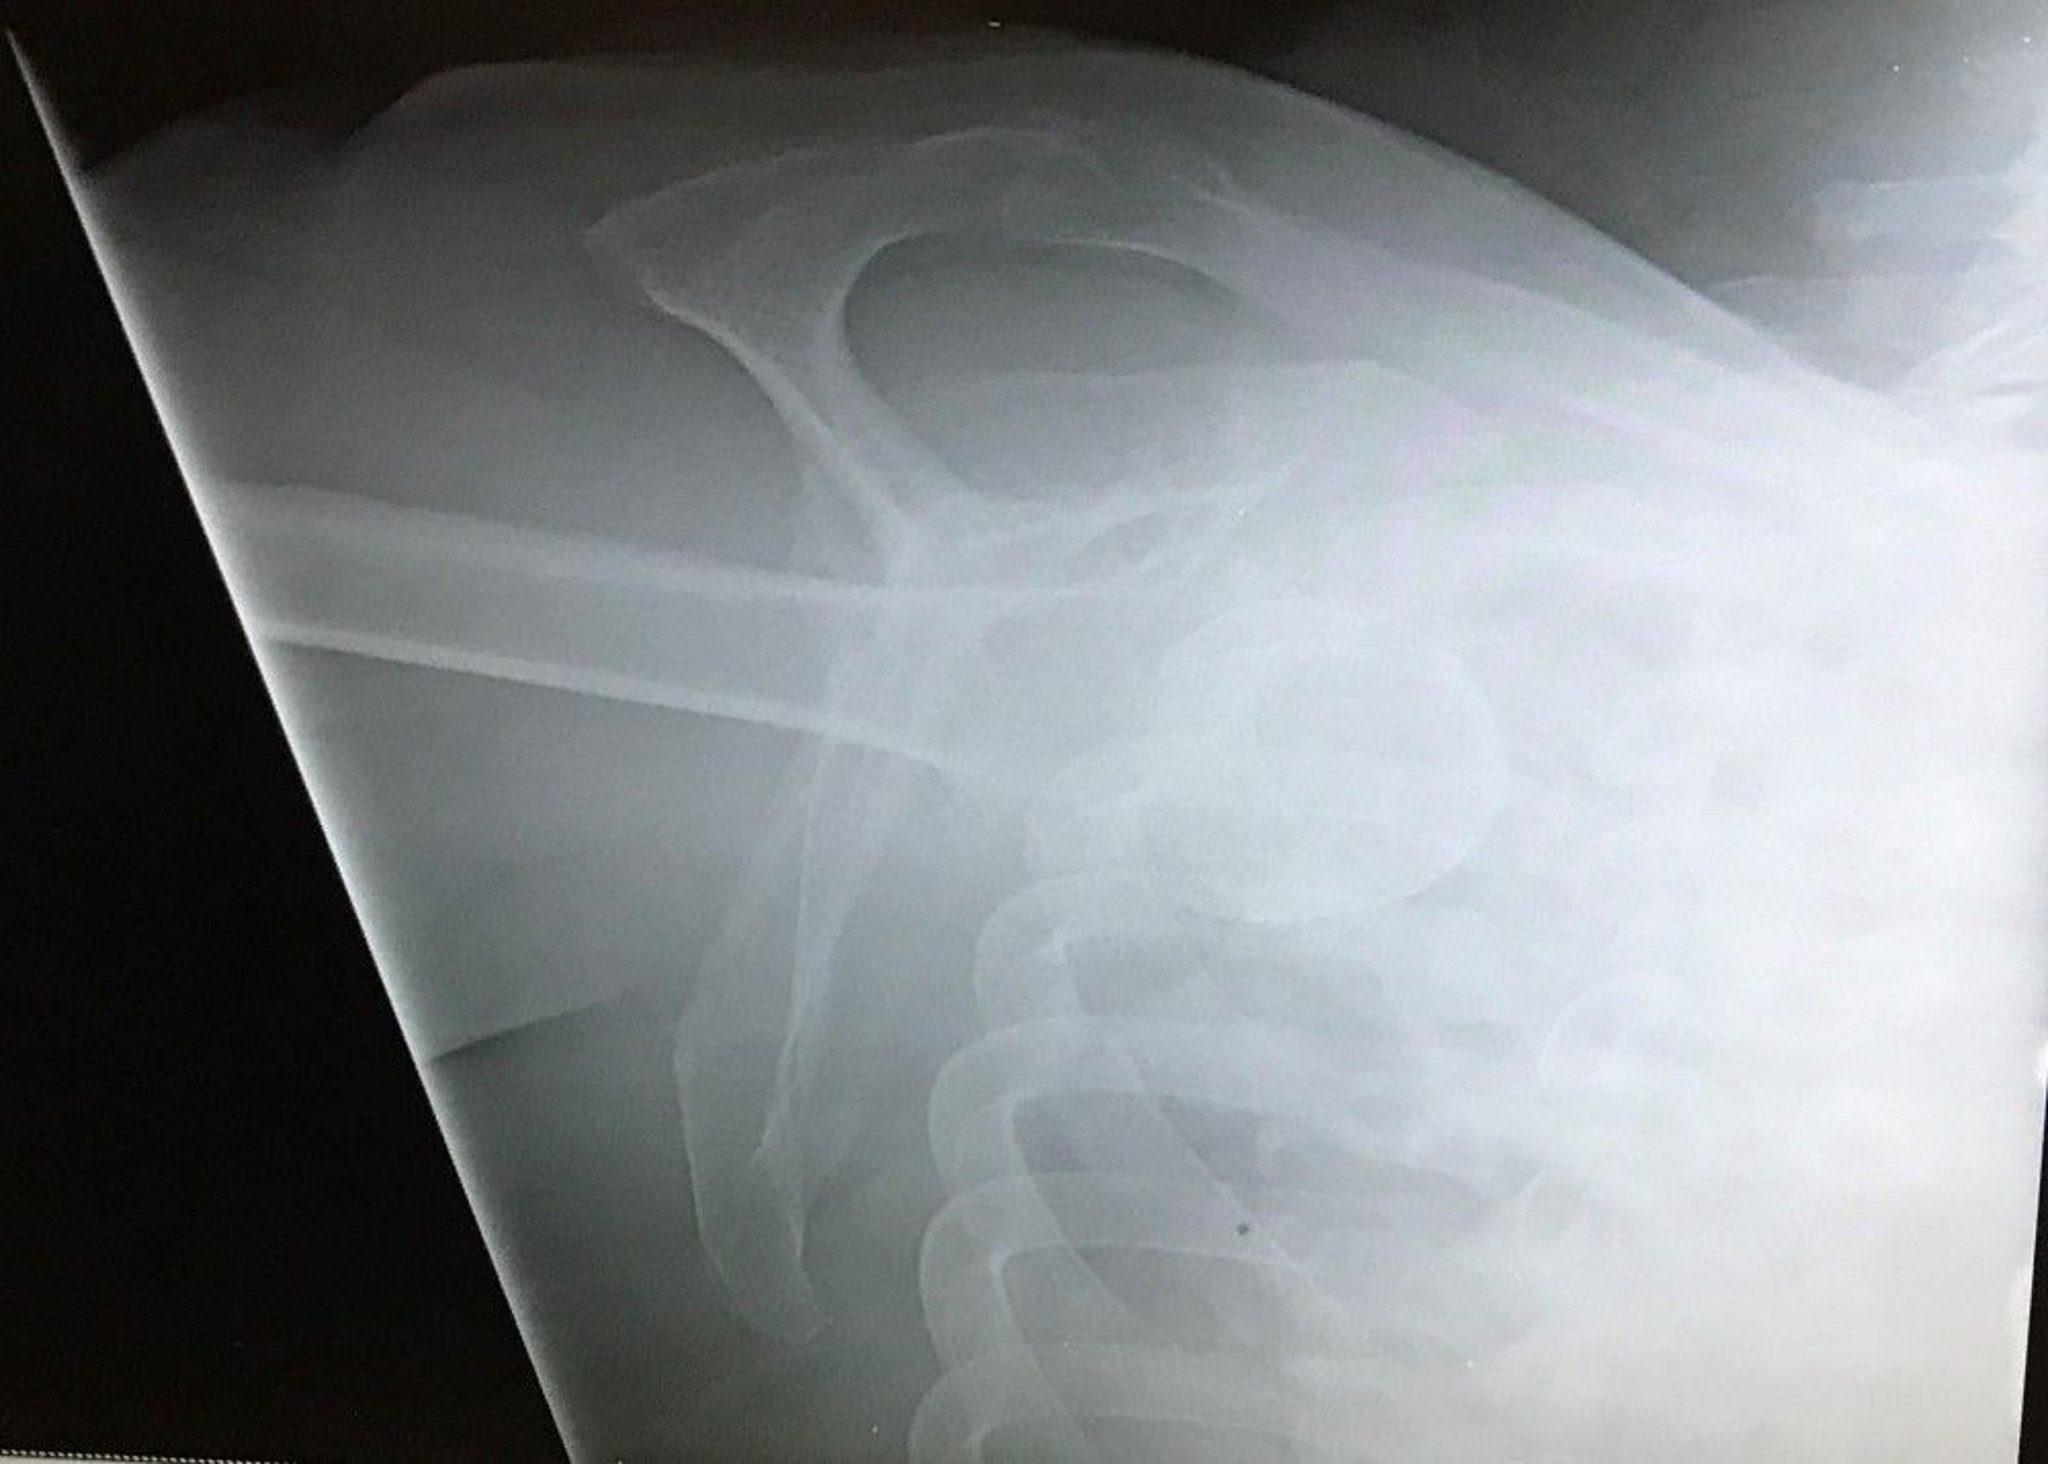

Inferior Shoulder Dislocation

This Y-view of the shoulder shows the humeral head inferior to the glenoid fossa with the extremity aimed cephalad, indicating an inferior glenohumeral dislocation (luxatio erecta).

Image courtesy of Danielle Campagne, MD.